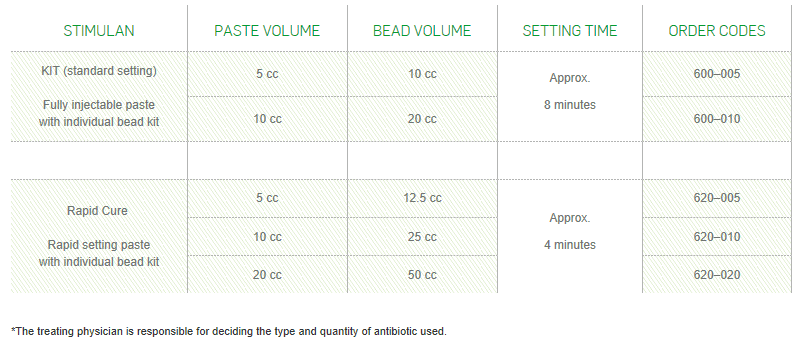

*The treating physician is responsible for deciding the type and quantity of antibiotic used. For indications, contraindications, warnings and precautions see Instructions for Use.

STIMULAN can be used in three sizes of bead, as a paste or for injection, to optimise packing in bone and soft tissue. Its hydrophilic properties and options of rapid or standard setting times make it quick and easy if mixed with one or more antibiotics – helping you to adapt to each case as is merited.*